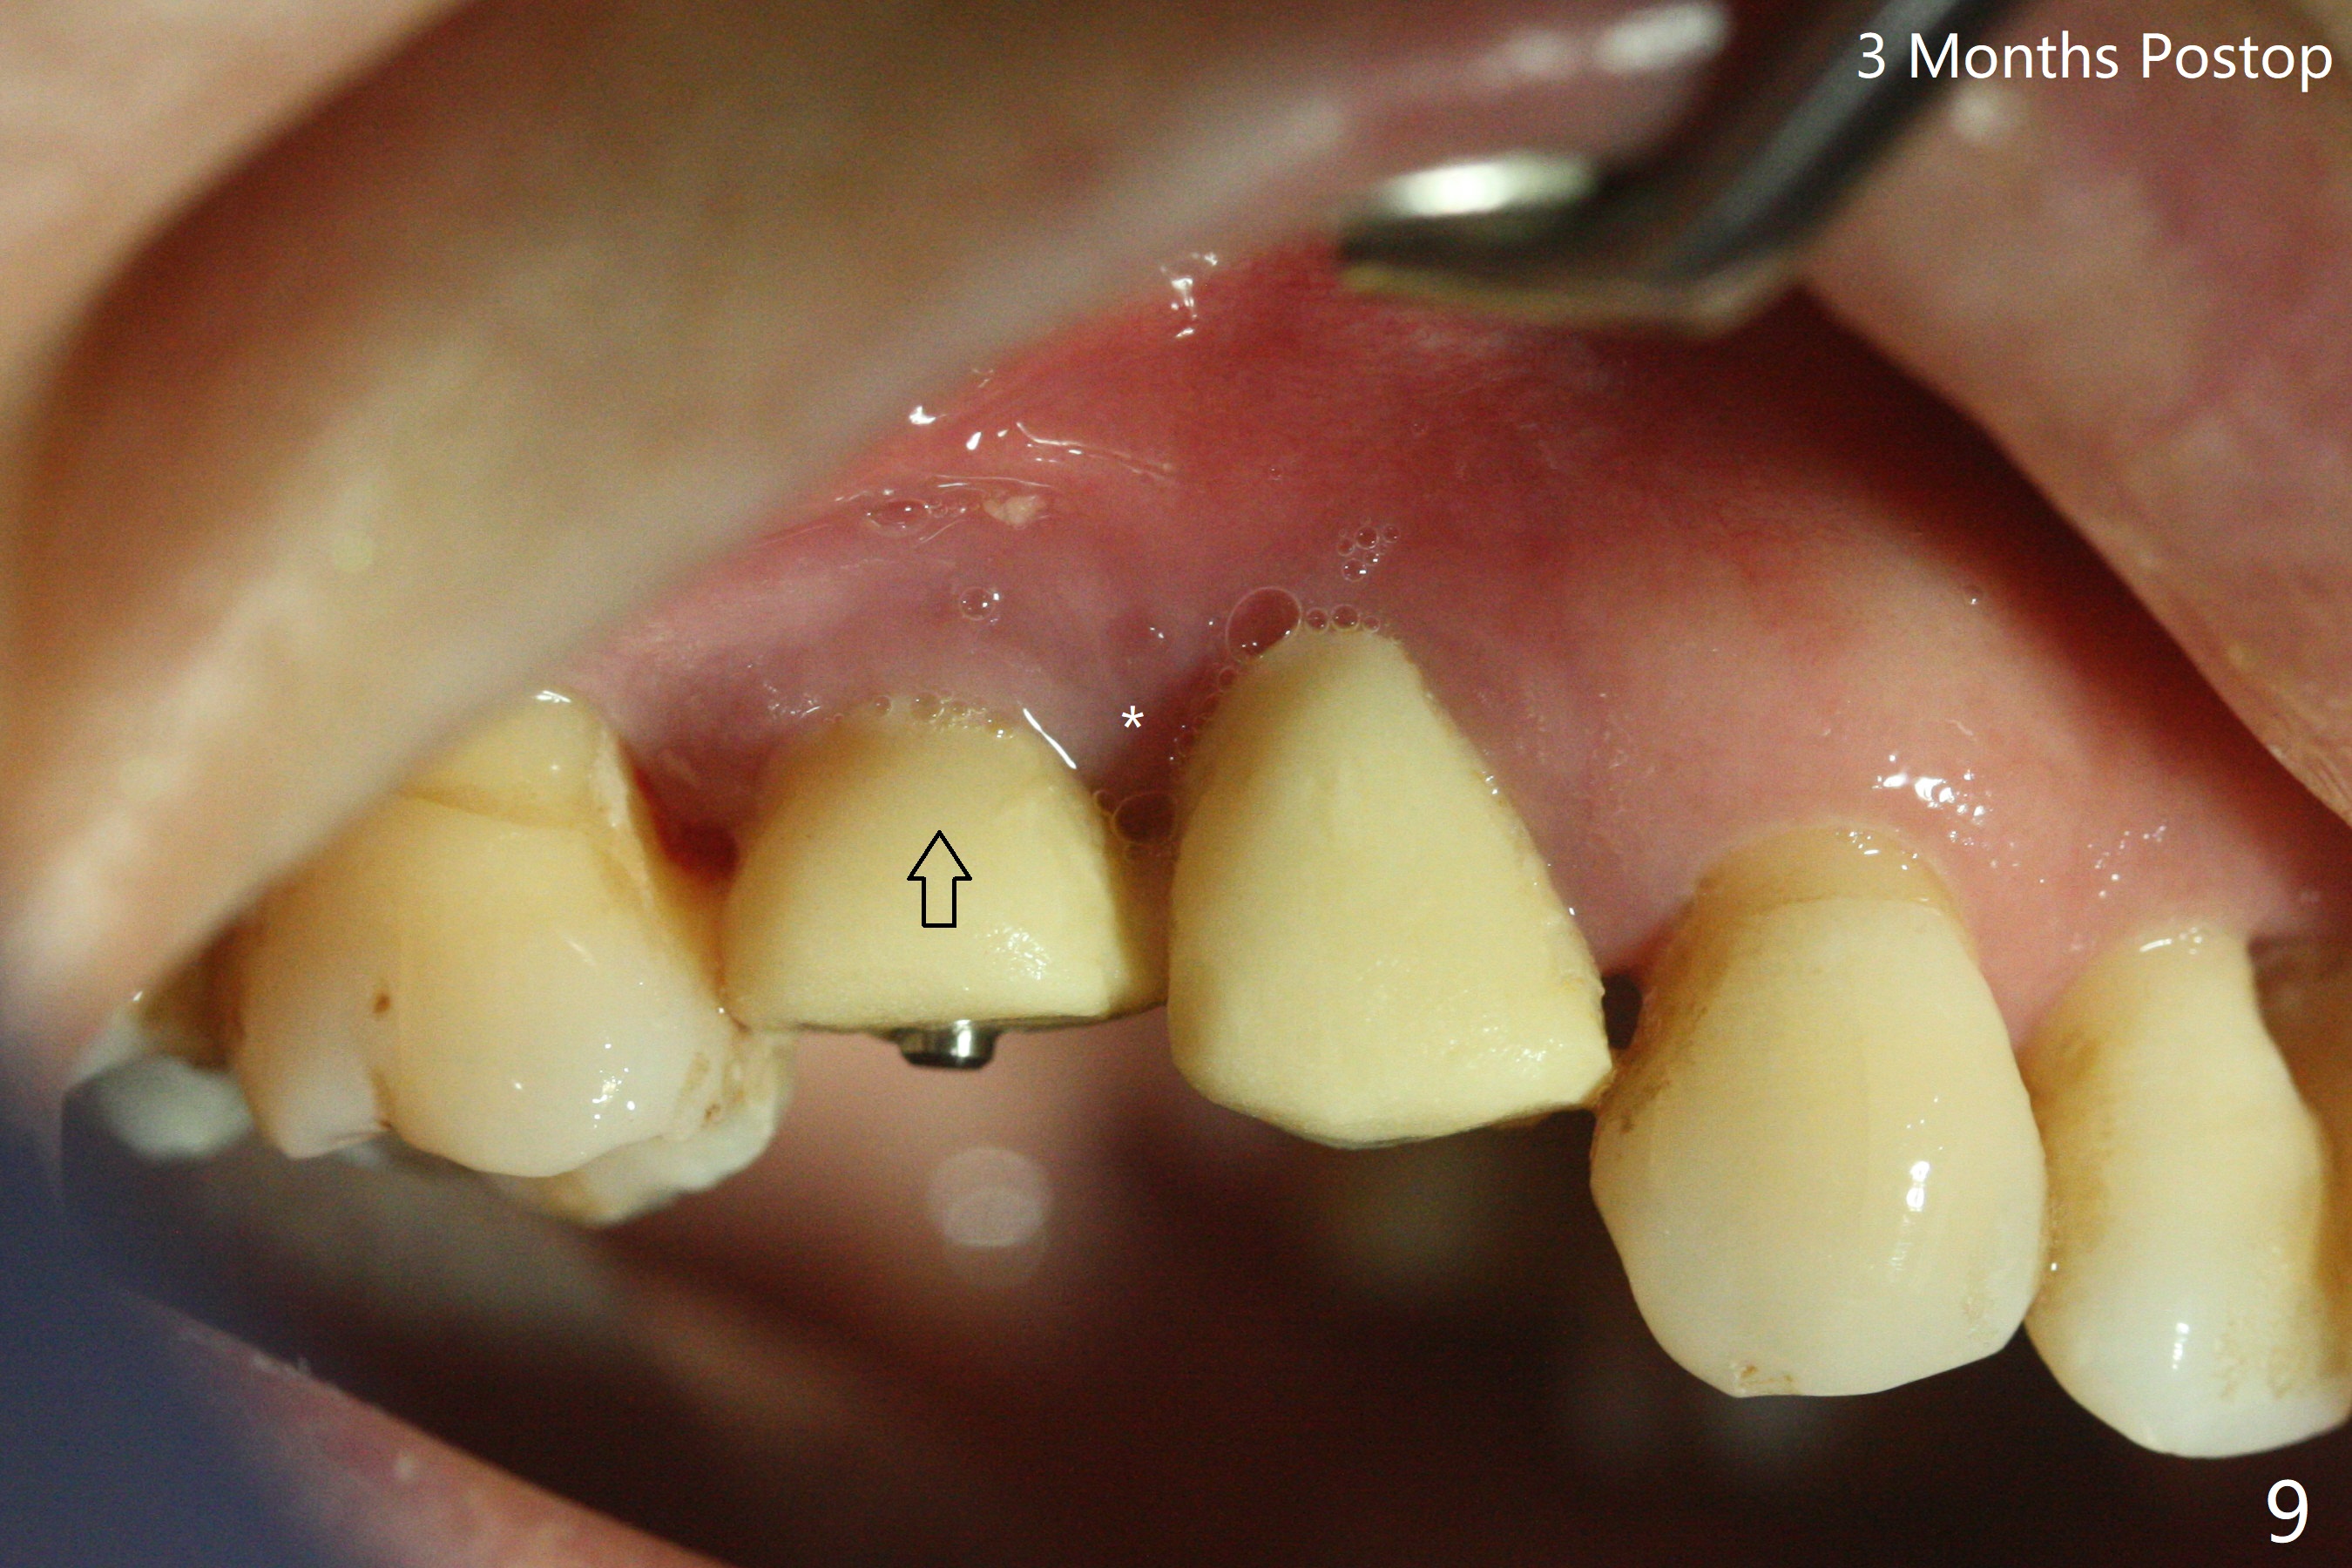

术前CT显示右上4牙槽骨比5窄(图一,二),3.5毫米植体比较合适,况且牙龈厚,基台长的一段式植体显得得当。为了取得最好的植体方位,4先拔除(图三),种植(图四),调整后者深度后,拔除5(术前征求病人同意),开始钻洞(图五),完成种植(图六)。粘性骨粉不仅放置于植体周围,而且6牙根近中(图七),4/5牙槽嵴和龈乳头(P)之间,减少术后龈乳头萎缩(图八:*)。制作两个分开临时牙冠,有利于维持龈乳头。对于病人来说,临时牙冠帮助咀嚼,而对侧拔牙创无法吃饭。术后3个月两个分开临时牙冠(其中一个龈方移位(图九:箭头)保持龈乳头(*)和牙龈外形(图十:*)。临时牙冠取出后,调整基台高度,少量钛屑(不妨大局)附着在健康的牙龈沟(图十一),再次显示两个基台之间龈乳头(图十二:*),衬里,修整的临时牙冠又插回牙龈沟(图十三:箭头),继续维持软组织形态,准备一个月后,调整基台边缘(图十二:箭头),取模。术后五个月大部分骨粉依然保留在植体和邻牙周围,龈乳头退缩不多(图十四: P)。三个月后(术后六个月)钛削无影无踪(图十五,与图十一对比))。永久性牙冠周围空间慢慢会消失(图十六,使用临时性胶水)。